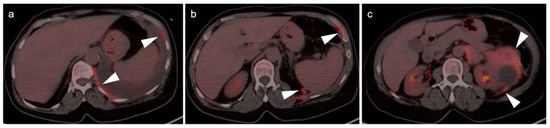

- Fuser, D.; Hedberg, M.L.; Dehner, L.P.; Dehdashti, F.; Siegel, B.A. Extensive Metastatic Sarcomatoid Renal Cell Carcinoma Evaluated by 18F-FDG PET/CT: A Case Report and Review of Literature. J. Kidney Cancer VHL 2018, 5, 1–6. [Google Scholar] [CrossRef] [PubMed]